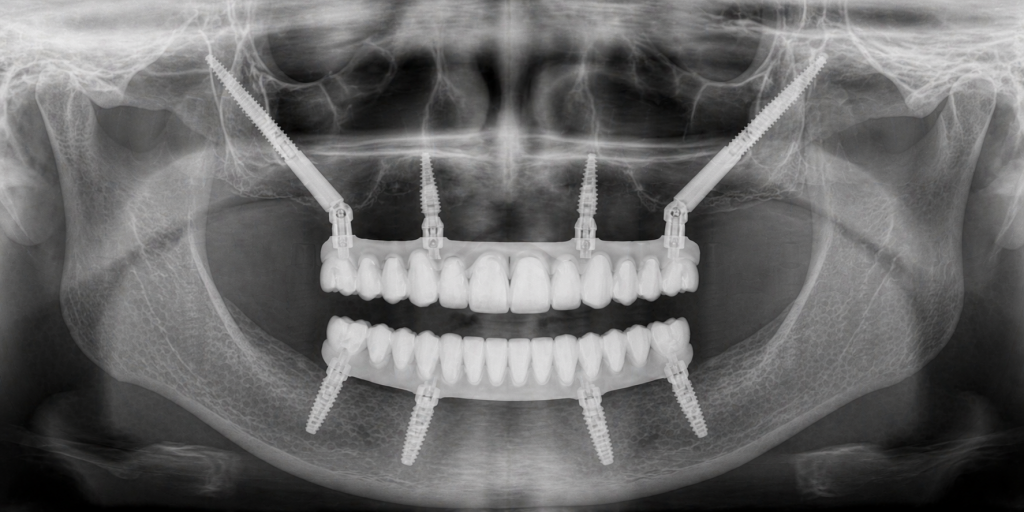

Cosa sono gli impianti zigomatici

Quando l’osso nella mascella superiore è molto ridotto,

gli impianti tradizionali potrebbero non essere sufficienti.

In questi casi esistono soluzioni più complesse, come gli impianti zigomatici. Sono impianti più lunghi, ancorati a un osso diverso (lo zigomo), che permettono di costruire una base stabile anche in condizioni ossee critiche.

Non sono indicati per tutti i pazienti, ma rappresentano una possibilità in situazioni selezionate.